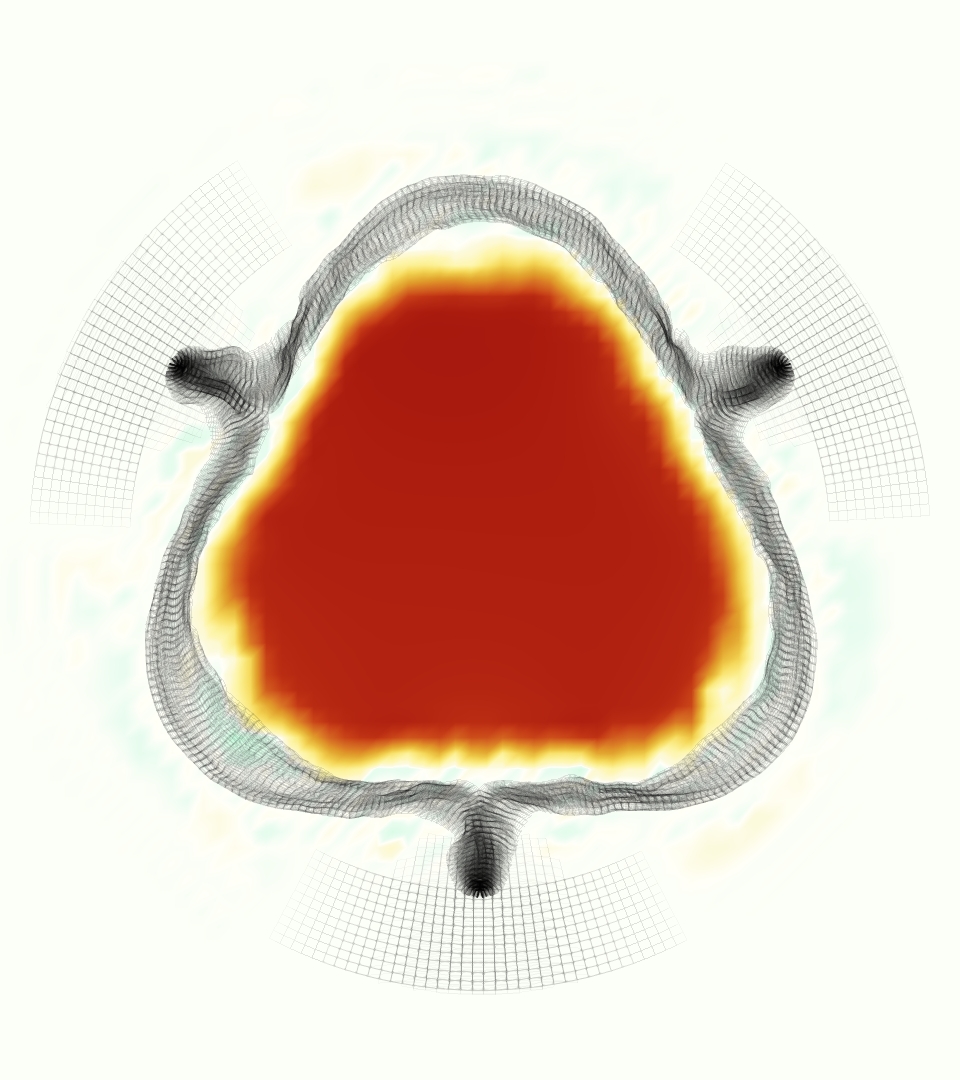

The gross morphology of the model valve that emerged from this process is shown in Figure 4. The free edge was 2.87 cm, corresponding to 3.3 cm in the predicted loaded configuration. After the pinching the leaflets together at the commissures, this left approximately 2.1 cm of free edge rest length per leaflet free to move independently of the other leaflets, within measurement error of ±0.1 cm from the free edge length of 2.2 cm measured on the prostheses. The leaflet rest height was 0.94 cm corresponding to a predicted loaded height of 1.44 cm. The measured leaflet height of 1.3 cm is nearly the predicted loaded height of 1.44 cm, which may be because the leaflets are so compliant in the radial direction, that pulling them flat to measure them achieved substantial stretches. The fiber orientation of the model runs from commissure to commissure and qualitatively matches experimental observations [38], though direct quantitative comparison is beyond the scope of this work. One minor limitation is that we do not add bending rigidity to the leaflets, beyond what emerges from the thickening process described above, and thus may not accurately capture leaflet flutter or other similar behaviors. Based on the thickness of mm, we estimated the mean tangent modulus at the predicted loaded stretches as dynes/cm2 circumferentially and dynes/cm2 radially. The prosthetic valve tissue is fixed in glutaraldehyde, and literature values for the fully-recruited circumferential tangent modulus of fixed porcine aortic valve tissue vary widely. Based on the experimental measurements of Billiar and Sacks and their constitutive law for valves fixed under 4 mmHg of pressure, we evaluated their constitutive law at the relevant stretches and and estimated the circumferential tangent modulus to be dynes/cm2 [6]. Rousseau et al. reported moduli ranging from to dynes/cm2, depending on the applied preload during fixation [36]. Sung et al. reported moduli ranging from to dynes/cm2, depending on fixation pressure [43]. Thus our estimated tangent modulus falls within the range of existing studies, so we considered our resultant modulus in good agreement given the complexity of the steps involved, phenomenological nature of the constitutive law and uncertainties in experiments. We do not have access to the precise material properties of the prosthetic valve, and further, the only literature we could find on the material properties of a similar prostheses reported the tangent modulus at one particular loading, which did not appear to be at a relevant stretch for comparisons with our model [19]. Thus, our model has material properties in a reasonable range for a fixed aortic valve prostheses (placed in the pulmonary position in our simulations), but it does not directly model the material properties of the prostheses.

We constructed the model vessel for FSI simulations from data from the MRI scans (Figure 4). The signal magnitude of 3D printed model material is distinct from the signal of the fluid in the scans, and we applied a thresholding operation to generate a three-dimensional model of the printed vessel surface. Using the MRI data ensured that the MRI and simulation coordinates were consistent in space and there were no alignment or registration errors. While using the files that generated the 3D printed model would have offered more spatial fidelity, the potential error in flow fields due to any mis-registration would have likely been much more substantial. Using Meshmixer (San Rafael, CA), we smoothed the mesh to remove stair-step effects and removed artifacts from the valve scaffold. We then remeshed to the desired edge length of 0.25 mm and extruded the model 0.25 mm and 0.5 mm to create a three-layer structure. As in the valve, this serves to eliminate the “grid aligned artifact” that can occur with pressure differences across thin membranes in the IB method [16]. Flow extenders of length 1 cm were added to the vessel at the inlet and both outlets to ensure that the normal to the vessel was aligned with the normal of the fluid box at the inlets and outlets. In FSI simulations, the vessel was held in place using target points, stiff springs of zero rest length that connect the current position of each model node to its desired position (Section 3.3). Additional linear springs are placed on each edge in the triangulated model. These springs are not meant to model a particular material and only serve to keep the vessel rigid and stationary throughout the simulation.

At = 0, the axial slice directly at the valve annulus shown in columns 1 and 2 in Figure 6, there was excellent agreement between the simulation and experiment over the cardiac cycle in the speed and shape of the jet through the valve. In both cases, the axial velocity increased as the flow accelerated during systole and the valve leaflets opened, then decreased during diastole with slight negative velocity before the valve leaflets were fully closed. The forward flow through the valve annulus did not form a full circle, but rather developed a triangular shape with a point of the triangle forming along the interior curve of the vessel, at the bottom of the axial slices. At = 0, the points of this triangular jet shape aligned with the commissures of the valve. This shape persisted during peak systole and was well-matched by the simulation.

The axial slice = 0.625 cm, shown in columns 3 and 4 in Figure 6, cut through the support scaffolding of the valve and the leaflets when they are open. In the experimental data, the shape of the jet changed as it moved downstream. A triangular shape occurred, but the points were then aligned with the middle of each open leaflet as opposed to the commissures. Those points were also more rounded than they were at = 0. The peak velocity of the jet was faster at = 0.625 cm than at = 0, as the flow accelerated through the open valve leaflets. The simulation produced these features at = 0.625 cm. The triangular shape of the jet shifted similarly, and its speed increased compared to the upstream slice. As the flow decelerated into diastole, the jet shape remained roughly triangular but diminished in intensity before disappearing after valve closure.

The jet continued to develop at = 1.25 cm, an axial slice immediately downstream of the valve scaffolding and open leaflets, shown in columns 5 and 6 in Figure 6. In the experimental data, the points of the triangular jet shape extended further towards the vessel wall. In addition, regions of reversed flow developed in the locations downstream of the commissures, resulting in curved sides to the shape of the jet. Each tip of the jet was unique, due to variations in the individual leaflets in the physical bioprosthetic valve. These variations are apparent in the velocity fields, possibly because the jet edges are similar enough cycle to cycle that irregularities are still being captured even with phase averaging. Further discussion of these features can be found in Schiavone et al. [39], which showed that the jet tip shapes occurred in different pulmonary anatomies, demonstrating that they were likely due to inherent properties of each leaflet. The leaflets in the mathematical model of the valve are identical, so these nuances in leaflet variation could not be replicated. The simulation did capture some of the extension of the tips of the jet, as they were closer to vessel wall at slice = 1.25 cm than = 0.625 cm. The curves in the triangular sides of the jet were also present in the simulation, though they were less pronounced than the experimental data. At both = 0.625 cm and = 1.25 cm, the jet shape in the simulation was smoother than the jet in experiment. It is possible that the free edges of the leaflets in the mathematical model are not fully replicating the behavior of the physical leaflets of the bioprosthetic valve, in particular the amplitude or frequency of leaflet flutter, leading to the variations seen in the jet shape at = 1.25 cm downstream of the leaflet edges. The simulation, however, does capture the key features of the triangular shape and speed of the jet. Overall, qualitative comparisons demonstrated that the simulation reproduced key features of the flow during systole and diastole.

The phase-averaged, resampled velocity fields during peak systole and flow rates at each resolution are shown in Figure 10. Despite the limitations discussed above, we observe similar qualitative trends in the flow field at all resolutions. At all resolutions, a jet formed and angled up downstream of the valve orifice, as shown in the sagittal view. The jets showed a triangle-like cross section at with points aligned with the commissures. At cm, the jet appears like a rounded triangle in the opposing orientation, with its points aligned with the center of the leaflets. At cm, the jet is narrower downstream of the commissures, and wider downstream of the leaflets, again with a triangle-like cross section. The area of the jet increased with resolution, as expected given the IB method thickening of the valve structure. The narrowed jets at the two more coarse resolutions show locally elevated velocities relative to the two more fine resolutions. Figure 11 shows the instantaneous velocity fields at each resolution in the same axial and sagittal views. At 0.9 mm, the sagittal view shows a qualitatively different jet than at finer resolutions, with regions of lower velocity farther from the vessel wall, indicating insufficient resolution. At 0.9 and 0.68 mm, the jet is visibly narrowed compared to higher resolutions. While some features are similar at these two coarse resolutions, we conclude that the narrower jets indicate these simulations are under-resolved. Flows in the three finest resolutions, 0.45, 0.34 and 0.28 mm. appeared qualitatively similar, with slightly more fine structure detail in both the axial and sagittal views present at the edges of the jet. The jets in the axial views all showed a similar triangle-like cross section, slightly narrower downstream of the commissures, as in the phase-averaged fields. In both the phase-averaged and instantaneous fields, the three finest resolutions appear sufficiently similar that the conclusions of this study would be identical with any of these resolutions.